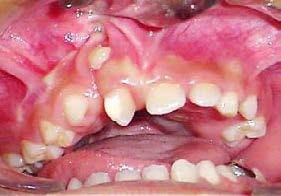

Caries y pérdida dental

La formación de caries en la dentición decidua y la consecuente pérdida prematura de órganos dentales deciduos, en algunas ocasiones, son

consideraciones a tomar muy en cuenta como factor etiológico en la inclusión del canino (Figura 32).

Por un lado, la presencia de caries interproximales en dientes deciduos, ya sea de manera independiente o como consecuencia de caries rampantes en uno o varios dientes, propicia la disminución de la longitud y/o perímetro del arco dental, donde ya no habrá, en consecuencia, el espacio necesario para el acomodo definitivo de los caninos y premolares permanentes.14

Por otro lado, al haber una pérdida prematura de un diente deciduo, además de generar una disminución de la longitud del arco dental, la biomecánica fisiológica propia de nuestro organismo, tiende a cerrar los espacios o brechas generadas por la pérdida de algún órgano dental, mesializando los dientes distales al diente faltante y generando extrusión del antagonista inmediato (Figura 33).

En consecuencia, los dientes que están en formación en cualquier periodo de Nolla quedaran atrapados dentro del hueso basal, con

La formación de caries en la dentición decidua y la consecuente pérdida prematura de órganos dentales deciduos, en algunas ocasiones, son consideraciones a tomar muy en cuenta como factor etiológico en la inclusión del canino.

posibilidades limitadas o nulas de acceder al hueso alveolar y erupcionar en la posición correcta, donde los caninos por todo lo mencionado anteriormente, son los más afectados.13